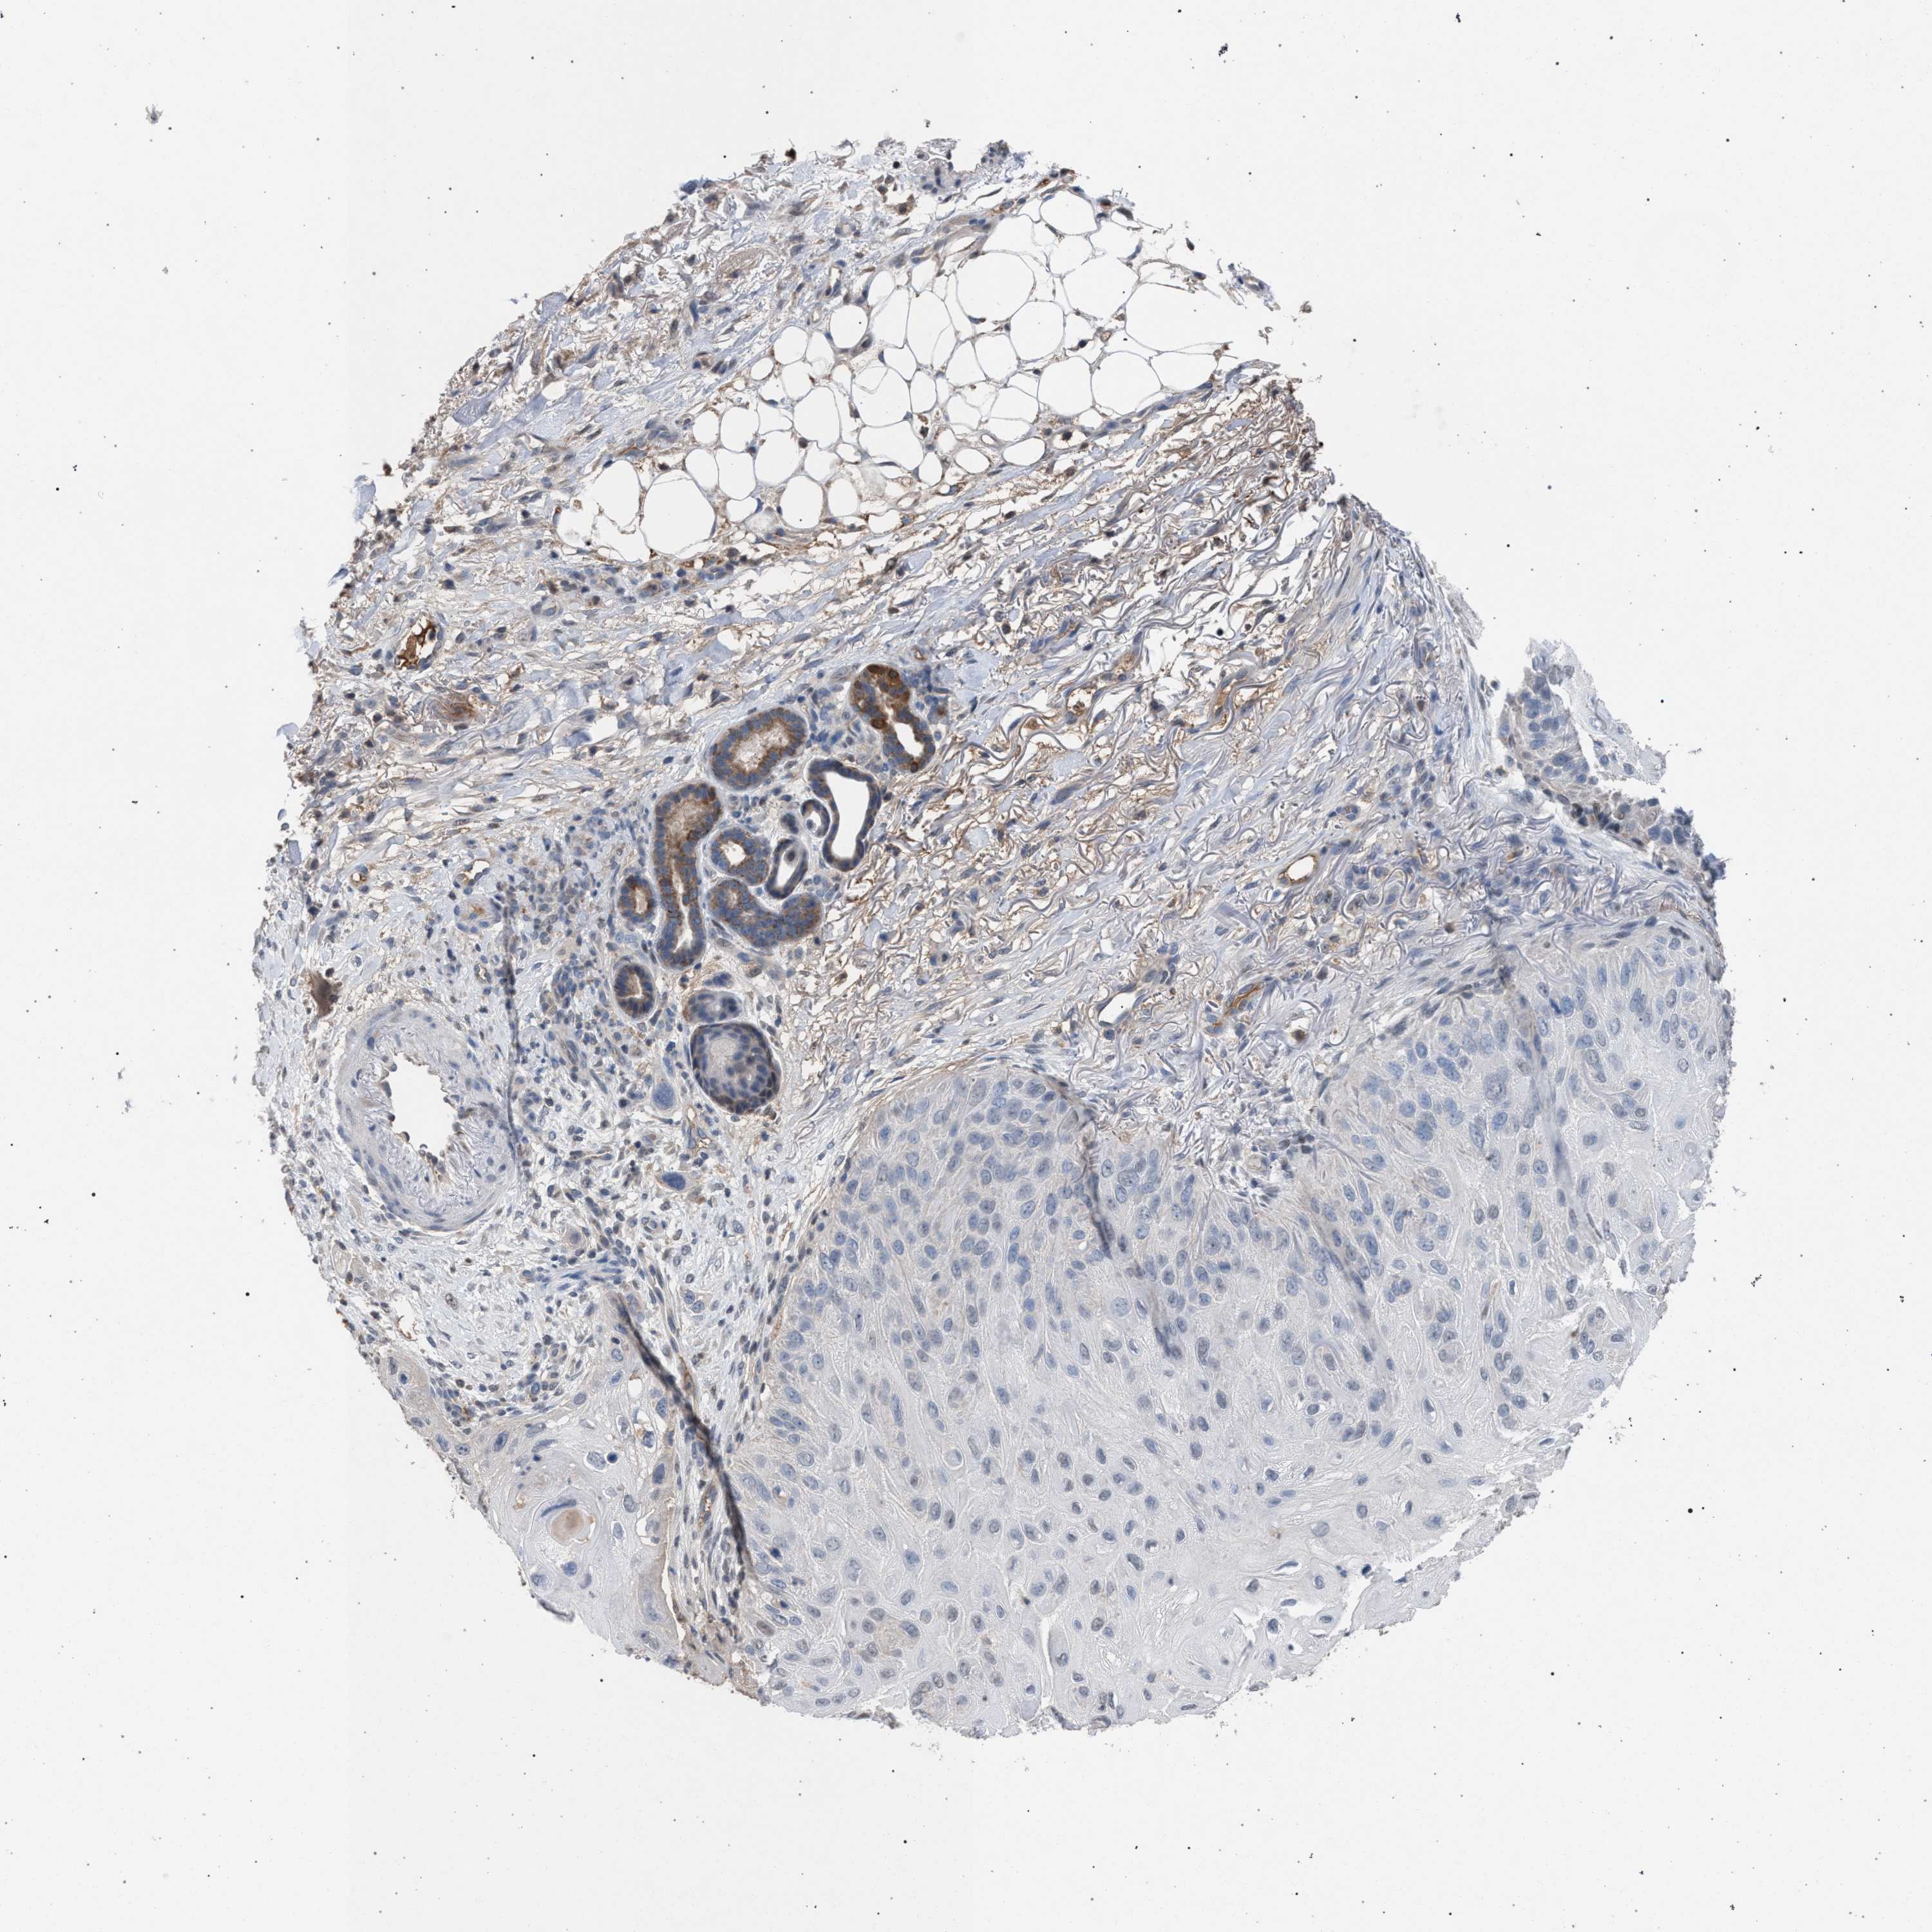

SKIN CANCER - Protein expressioni

A mouse-over function shows sample information and annotation data. Click on an image to view it in a full screen mode. Samples can be filtered based on level of antibody staining by selecting one or several of the following categories: high, medium, low and not detected. The assay and annotation is described here.

Antibody staining in the annotated cell types in the current human tissue is reported as not detected, low, medium, or high, based on conventional immunohistochemistry profiling in selected tissues. This score is based on the combination of the staining intensity and fraction of stained cells.

Each image is clickable and will lead to virtual microscopy that enables deeper exploration of all samples and also displays staining intensity scores, fraction scores and subcellular localization as well as patient and tissue information for each sample.

Antibody HPA021061

Staining

High

Medium

Low

Not detected

Intensity

Strong

Moderate

Weak

Negative

Quantity

>75%

75%-25%

<25%

None

Location

Nuclear

Cytoplasmic/membranous

Cytoplasmic/membranous,nuclear

Basal cell carcinoma

Squamous cell carcinoma, NOS

Squamous cell carcinoma, metastatic, NOS